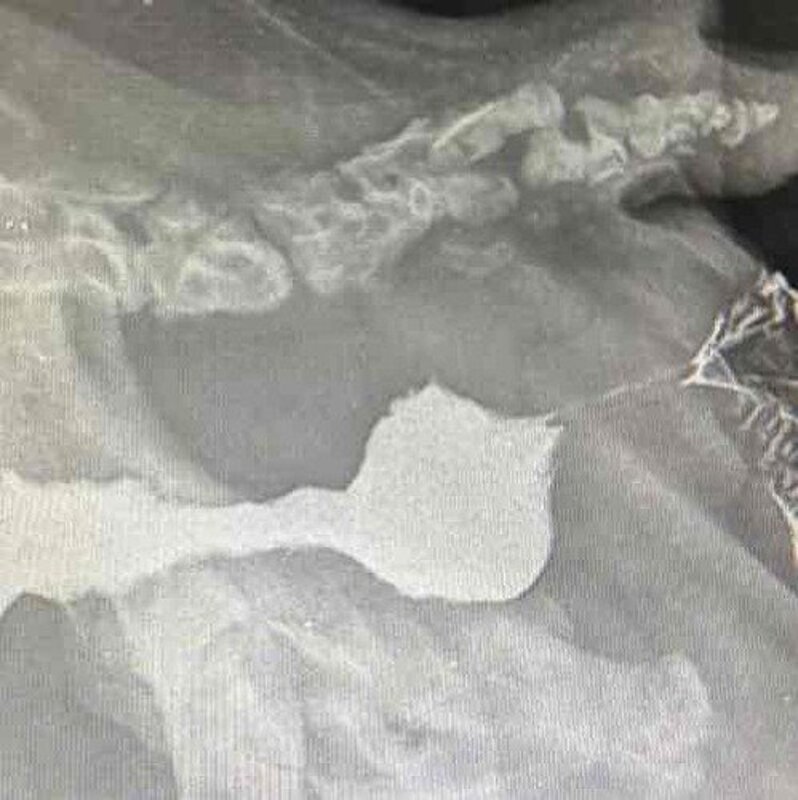

NOTÍCIAS URGENTES DO CACOEsse pequeno é o caco, está a mais ou menos uns 40 dias no projeto, ele veio para nós já operado, com uma cirurgia de prolapso, porém quem fez essa cirurgia acabou fazendo algo errado no procedimento e que só piorou o quadro dele.Ele chegou com muitas dores , e defecando líquido sem parar , além de ter giardia e colite, logo internamos ele e descobrimos que ele só tinha abertura de 0,04 cm para passagem das fezes , e desde então estamos tratando dele, ficou internado por muitooos dias, e agora estava em lt e teve uma grande piora, foi internado às pressas e agora sua continha lá está 4 mil reais 😨 além dos 3 mil que ainda falta pagar na outra clínica.Ele foi operado e foi tudo muitooo delicado, agora torcemos que ele melhore mas é um caso grave!!CONTAMOS COM APOIO DE TODOSVAKINHA NA BIO